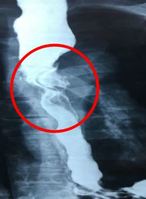

- ½É±Ù°æ»öÀ¸·Î ¿ÀÀÎÇϱ⠽¬¿î ´ëµ¿¸Æ¹Ú¸®´Â ´ëµ¿¸Æ Ç÷°üº®ÀÌ Âõ¾îÁö´Â Ä¡¸íÀû ÁúȯÀÌ´Ù. ƯÈ÷ »óÇà ´ëµ¿¸ÆÀ» ħ¹üÇÑ °æ¿ì 24½Ã°£ ³» ¼ö¼úÀÌ ÇÊ¿äÇÒ ¸¸Å ¿¹Èİ¡ ºü¸£°Ô ¾ÇÈÇÒ ¼ö ÀÖ´Ù.¡Þ»óÇà ´ëµ¿¸Æ ħ¹üÇÑ AÇü, Áø´Ü..